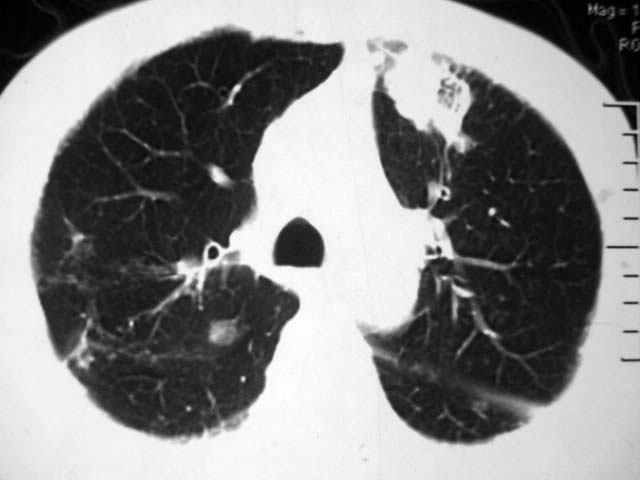

男,52岁,发热2月,糖尿病史。

抗结核治疗irpz方案,血糖未治疗,空腹15.9左右。症状无好转,左胸痛。

复查ct

2、双肺见多发片状及结节状高密度影,大多数病灶中心均见“空泡征”。

3、纵隔内淋巴结肿大。

结果:两肺继发性肺结核并曲霉菌感染。